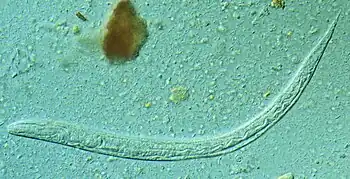

Diagnosis rests on the microscopic identification of larvae (rhabditiform and occasionally filariform) in the stool or duodenal fluid. Examination of many samples may be necessary, and not always sufficient, because direct stool examination is relatively insensitive, with a single sample only able to detect larvae in a small percent of cases. It can take 4 weeks from initial infection to the passage of larvae in the stool.The stool can be examined in wet mounts via a variety of methods[23][4][24]